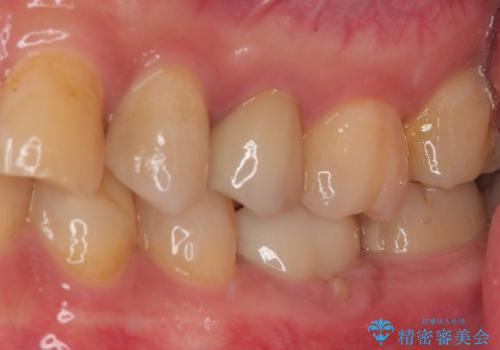

また、左上の4番目のメタルインレーが脱離しているところについては患者様のご希望により保険診療のコンポジットレジンにて修復しています。

違和感がなくなり、フロスも引っかからなくなり大変喜んでいただけました。